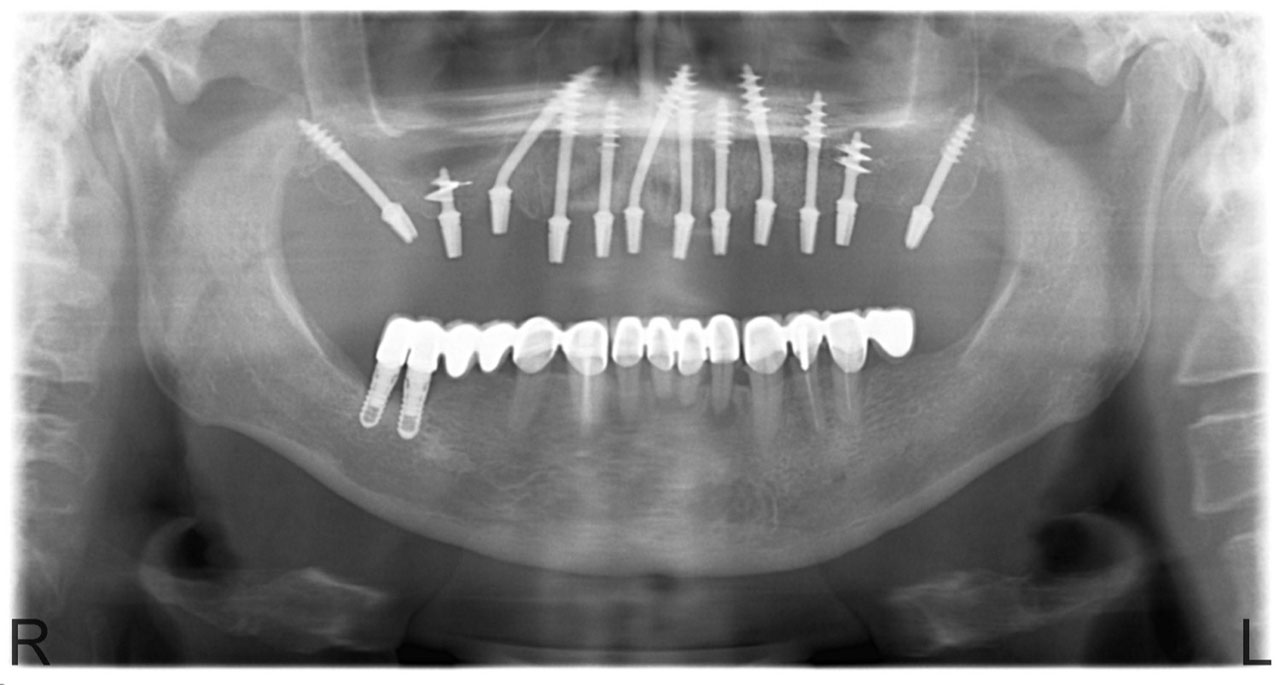

Sikerét mindenekelőtt a gyorsaságának köszönheti, hiszen a mai rohanó világban kinek van ideje, kedve fogatlanul otthon ülni heteket, hónapokat a fogpótlásra várva? Az Ihde implantációs eljárás során a páciens azonnal, de legkésőbb 72 óra múlva egy rögzített (tehát nem mozgó, nem kivehető) pótlással hagyja el a rendelőt. Ez az egyedülállóan gyors eljárás annak köszönhető, hogy azonnal tudunk implantálni szinte bárhova, akár foghúzás után is, továbbá a művelet nem jár nagy feltárásokkal, nincs szükség csontbeültetésre, így a gyógyulás folyamata is nagyon gyors és a beültetés technikájának köszönhetően maximum 72 óra múlva a korona is feltehető. Tehát ennyi idő alatt foga lesz a betegnek és az implantátum azonnal terhelhetővé is válik.

Az eljárás mellett szól az is, hogy nagyon biztonságos. A cég adatai alapján a beültetett implantátumok 98.2%-a sikeres. Az azonnali terhelésű implantátumokkal rögtön, akár foghúzás után is szinte bárhová lehet implantálni, bárkinek, legyen szó cukorbeteg, dohányos, vagy akár csontritkulásban szenvedő páciensről. Ennek köszönhető, hogy a betegek 99%-ánál alkalmazható a módszer.